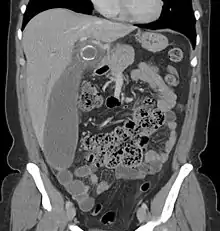

Coronal CT scan of a person initially suspected of having appendicitis because of right-sided pain. The CT shows in fact an enlarged inflamed gallbladder that reaches the right lower part of the abdomen.

Children: Gastroenteritis, mesenteric adenitis, Meckel's diverticulitis, intussusception, Henoch–Schönlein purpura, lobar pneumonia, urinary tract infection (abdominal pain in the absence of other symptoms can occur in children with UTI), new-onset Crohn's disease or ulcerative colitis, pancreatitis, and abdominal trauma from child abuse; distal intestinal obstruction syndrome in children with cystic fibrosis; typhlitis in children with leukemia.

Women: A pregnancy test is important for all women of childbearing age since an ectopic pregnancy can have signs and symptoms similar to those of appendicitis. Other obstetrical/gynecological causes of similar abdominal pain in women include pelvic inflammatory disease, ovarian torsion, menarche, dysmenorrhea, endometriosis, and Mittelschmerz (the passing of an egg in the ovaries approximately two weeks before menstruation).[63]

Men: testicular torsion

Adults: new-onset Crohn disease, ulcerative colitis, regional enteritis, cholecystitis, renal colic, perforated peptic ulcer, pancreatitis, rectus sheath hematoma and epiploic appendagitis.

Elderly: diverticulitis, intestinal obstruction, colonic carcinoma, mesenteric ischemia, leaking aortic aneurysm.

The term "pseudoappendicitis" is used to describe a condition mimicking appendicitis.[64] It can be associated with Yersinia enterocolitica.[65]